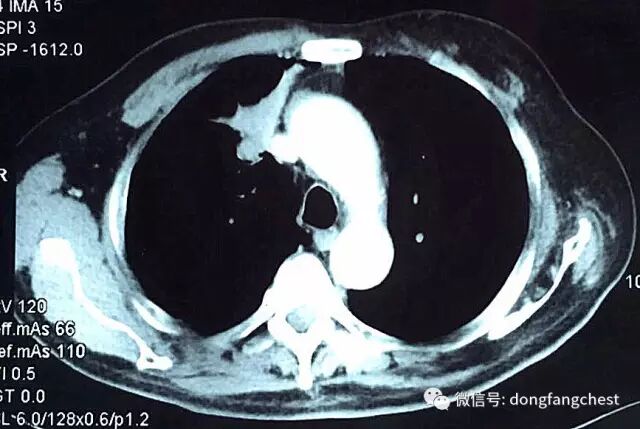

年近70岁的李老爷子,反复咳嗽了一个月不见好,于2016年12月在东方总院拍CT,检查发现”右肺上叶恶性肿瘤“。

由于肿瘤体积较大,且与肺动脉、上腔静脉关系紧密,手术实施起来较为困难,经过东方总院多学科讨论会诊,决定先于呼吸内科进行了2个疗程新辅助化疗。

化疗后,李老体内的肿瘤体积明显缩小,随后于2月22日进入总院心胸外科进行手术治疗。手术由总院胸外科朱胜主任、王鸿副主任、高涛涛医生共同完成。术中发现肿瘤侵犯右肺动脉干、上腔静脉部分血管壁。术中,经上腔静脉远端、右心房插管转流,阻断受肿瘤侵犯部位腔静脉后予以部分血管壁切除,然后取心包组织进行上腔静脉修补重建。